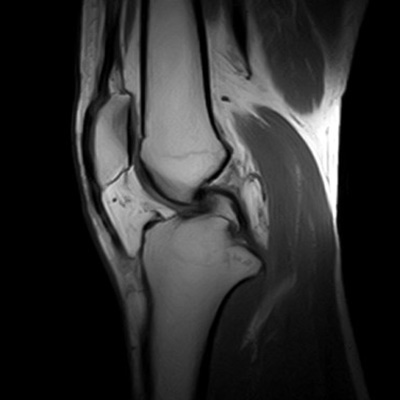

Es el estudio de estructuras anatómicas compuestas por huesos, musculatura, tendones, cartílago etc.

Ejemplos